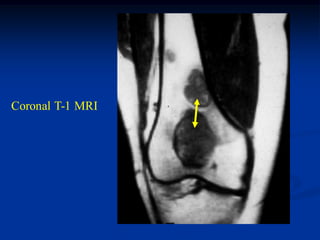

Coronal T-1 MRI

Sagittal T-1 MRI

Axial proton density MRI

Photomic

2 months post op

pins, cement and

cancellous allograft

allograft

Lateral view

cement